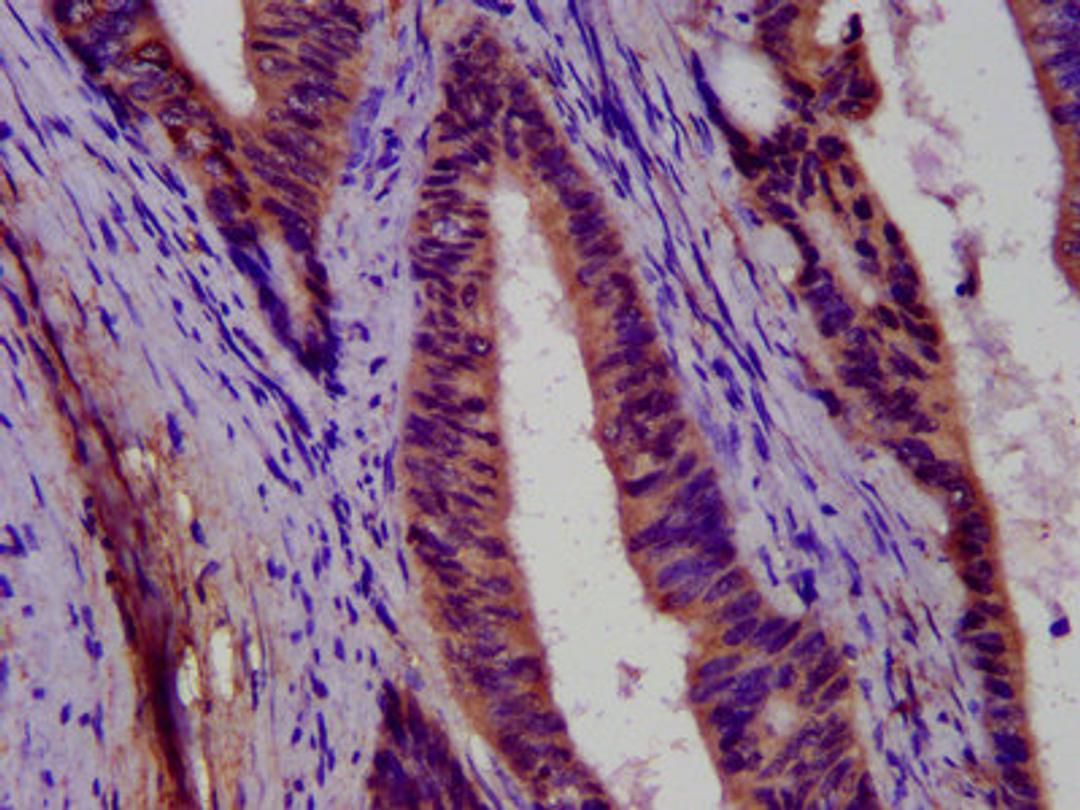

IHC image of CSB-PA866326LA01HU diluted at 1:500 and staining in paraffin-embedded human colon cancer performed on a Leica BondTM system. After dewaxing and hydration, antigen retrieval was mediated by high pressure in a citrate buffer (pH 6.0). Section was blocked with 10% normal goat serum 30min at RT. Then primary antibody (1% BSA) was incubated at 4°C overnight. The primary is detected by a biotinylated secondary antibody and visualized using an HRP conjugated SP system.